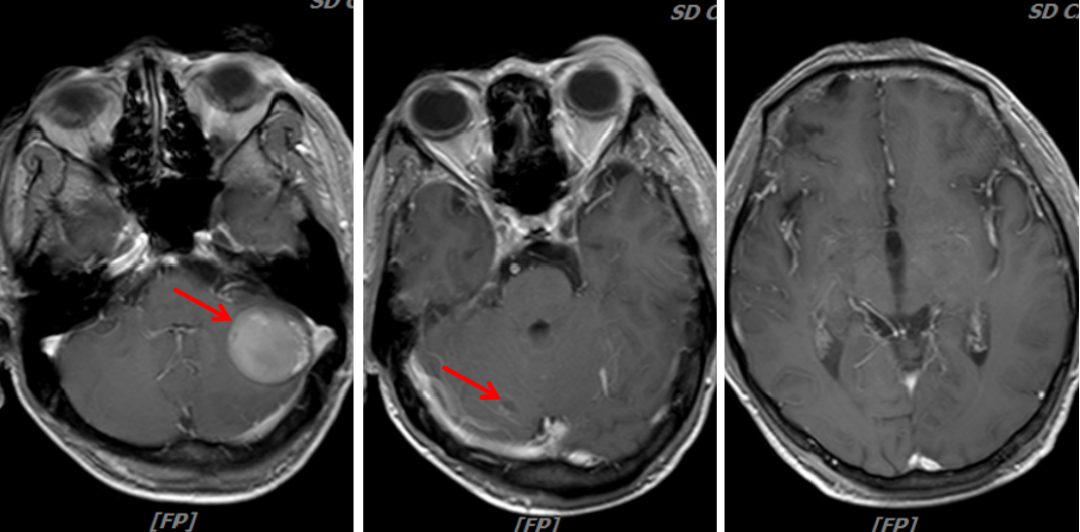

头颈MRI(我院):1.结合病史,脑多发转移瘤;2.筛窦炎。

图4:2020年1月30日,治疗前头颅MRI

图7:2020年3月25日,联合治疗2周期后头颅MRI

图9:2020年5月6日,联合治疗4周期后头颅MRI

病例二总结

本例患者为“左肺上叶小细胞癌(广泛期,cT3N1M1,IV期),伴左肺门淋巴结转移、多发脑转移”,考虑予以免疫联合化疗。为明确并监测患者可能出现的毒副反应,先予以患者1周期EP方案化疗,同时予以全脑放疗1个月。患者未出现明显不良反应,予以患者加用替雷利珠单抗免疫治疗2周期,疗效评价即达到PR,治疗6周期后疗效达到CR。随访至今PFS已超过7个月,疗效持续CR,安全性良好,患者可以耐受。